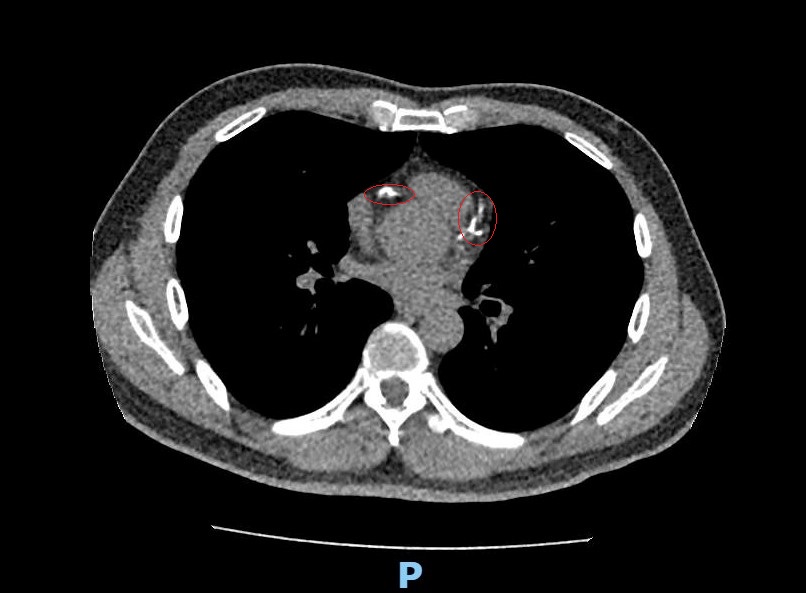

49歲事業有成的林先生日前進行低劑量電腦斷層肺癌篩檢(LDCT),意外發現心血管鈣化嚴重,進一步檢查才驚覺冠狀動脈竟有85%至100%的高度阻塞,引發急性心肌梗塞的風險極高。衛福部彰化醫院心臟科醫師李學林隨即以最新技術「血管內震波碎石術(IVL)」成功擊碎鈣化斑塊,並順利植入三支支架,讓血流重新暢通。

圖說:部彰以低劑量斷層掃瞄為林先生檢查 意外發現他的血管鈣化嚴重

部彰李學林醫師表示,林先生日前接受肺癌篩檢時意外發現心血管鈣化,但無法確認是血管內或血管外鈣化。因患者平時已出現胸悶症狀,進一步做心臟冠狀動脈電腦斷層,確認為3條主要冠狀動脈血管內鈣化狹窄達85%以上,若未及時處理,隨時可能引發急性心肌梗塞。

李學林指出,臨床上約有三成冠狀動脈疾病患者伴隨中重度血管鈣化狹窄,鈣化讓血管變硬、難以擴張,造成治療挑戰。相較於傳統治療如切割球囊或鑽石旋磨術,IVL對血管壁更為溫和,能有效降低血管破裂與剝離風險,安全性更高,但目前該技術尚未納入健保給付。而林先生本身具有三高、家族史及吸菸習慣,是典型的心血管疾病高風險族群,雖未發生急性心肌梗塞,但血管阻塞卻已悄悄累積。這次在肺癌篩檢中發現心血管鈣化,可說是「意外的及時預警」。

李學林表示,要看出心血管鈣化情況可以靠心臟冠狀動脈電腦斷層掃描,快速、無侵入性地檢測出心血管的鈣化程度,但必須自費且費用不低,如果能先做LDCT,不僅能篩檢肺癌,還能了解心血管的鈣化情況。政府目前針對「具肺癌家族史」、「具重度吸菸史」兩大肺癌高風險族群,補助每兩年一次的免費LDCT,一般人則需自費篩檢,現今很多人在安排健檢時也會將LDCT納入項目,成了健檢趨勢。